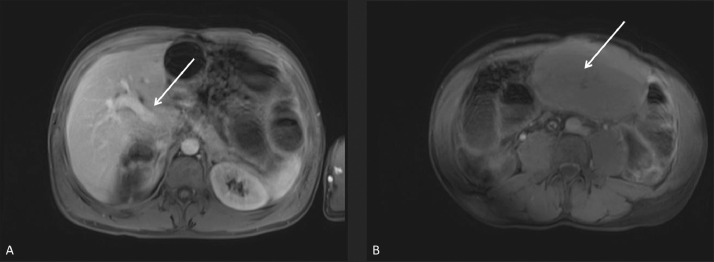

After further discussion between radiology and surgical teams, including pediatric surgery, the decision was made to obtain an enhanced MRI of the abdomen to help characterize the mass [Fig. 5, A-C], as well as rule-out other findings in this patient with known congenital defects. The MRI demonstrated a non-enhancing mass in the upper abdomen, which communicated with the undersurface of the normal appearing left hepatic lobe via a thin stalk. After review of the prior CTs [Fig. 6, A-B] and MRI [Fig. 7, A-B], it was determined that this stalk contained a vascular pedicle, which appeared twisted upon itself. This confirmed the suspicion of torsion of an accessory liver lobe.

A-B – (A-B) Contrast-enhanced, T1-weighted, axial MRI images show normal enhancement of the portal vein (arrow) compared to (B) no enhancement in the torsed ALL (arrow)..

MRI has the advantage over CT with its contrast resolution based on tissue characteristics rather than tissue densities. Because of this, the non-enhancing vasculature extending from the normal liver to the pedicle and into the accessory lobe could be more readily appreciated. The T2-signal was increased in the torsed accessory lobe indicating edema, which is consistent with an acute torsion. A chronic torsion would appear as cystic changes as the infarcted tissue atrophied. Through several different imaging modalities, the challenges of diagnosing such a rare entity are clearly demonstrated.